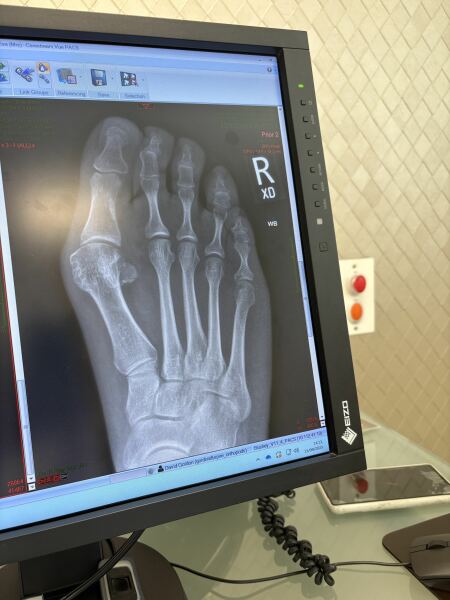

This is my right foot 6 months post surgery. The bone has healed around the screws. Surgeon confident with this technique (keyhole) rhey won’t come back

How the hell to cope with bunions?!

Really interesting to see the X-ray. Do you happen to have a before pic?